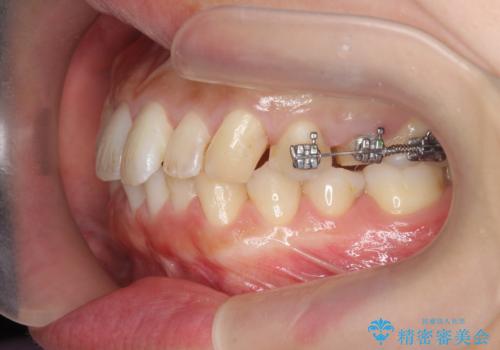

挺出小矯正を行った縁下カリエス治療

X線撮影を行い、隣接面に多発した虫歯と歯ぐきよりも深くなってしまった虫歯を小矯正をおこなったのちのセラミック治療で問題を解決します。

小矯正を行い深い虫歯を改善した後は、小手術を行うことで歯ぐき・周囲歯槽骨の状態を整えることでより安定した歯周環境を得ることができます。